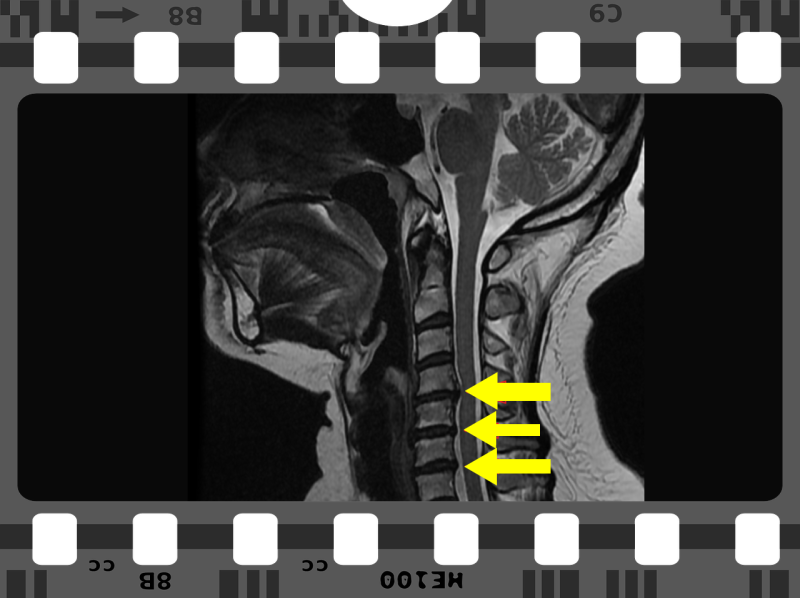

허리질환은 현대인들에게 흔한 문제로, 허리 통증이 지속되면 일상생활에 큰 지장을 줄 수 있습니다. 이러한 통증을 관리하는 데 있어 신경차단술신경성형술은 흔히 선택되는 대표적인 시술입니다. 두 시술의 차이를 이해하면 올바른 판단과 선택을 할 수 있습니다.

신경차단술은 진통제스테로이드를 특정 신경에 주입하여 통증을 감소시키는 시술입니다. 이 시술은 주로 경막외 강직증후군이나 디스크 탈출증으로 인한 통증 완화를 위해 사용됩니다. 주사로 약물을 직접 통증이 있는 부위에 주입하면, 신경의 염증을 감소시키고 통증을 완화하는 효과를 가집니다.

신경성형술은 통증의 원인이 되는 신경을 직접적으로 치료하는 방법입니다. 이 시술은 신경의 구조를 보강하기 위해 물리적 방법을 사용하여 신경의 정상적인 기능을 회복시키는 것을 목표로 합니다. 주입되는 물질은 신경에 직접적인 영향을 미쳐 통증을 경감시킴과 동시에 신경의 유연성을 증가시킵니다.